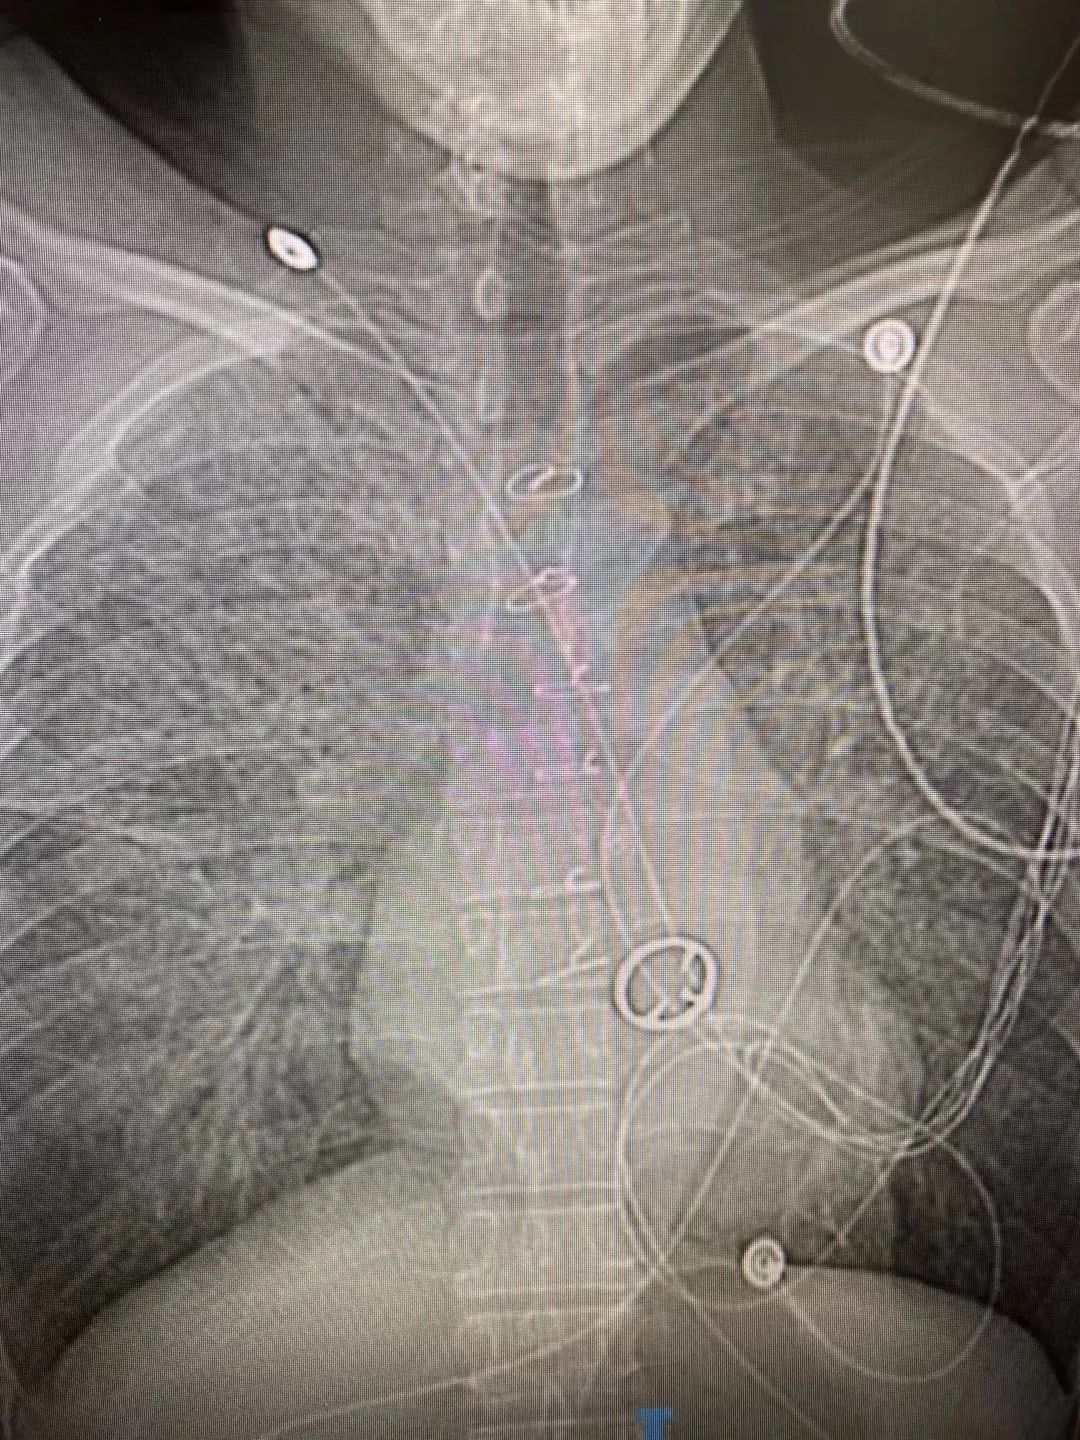

20年前他因心脏瓣膜病在外院做了二尖瓣机械瓣膜置换术,3月27日周六晚,他突发呼吸困难,被120车送往柳州市工人医院急诊科。由于病情危重,急诊科立即将罗先生送入重症监护室(简称ICU)监护病房。

经急诊心脏彩超检查,确诊为二尖瓣机械瓣膜开放严重受限。

此时,罗先生已经出现急性心衰症状,在大剂量血压药物作用下,血压仍低至70/40mmHg,并心跳随时可能会停止,尽快手术更换掉损坏的机械瓣膜是挽救他生命的唯一方法。

吴主任沉着冷静,凭着多年丰富的经验耐心的分离组织,打开心脏,取出了心腔内形成的大量血栓以及严重功能障碍的瓣膜,并为患者装上了新的人工瓣膜,手术顺利完成!